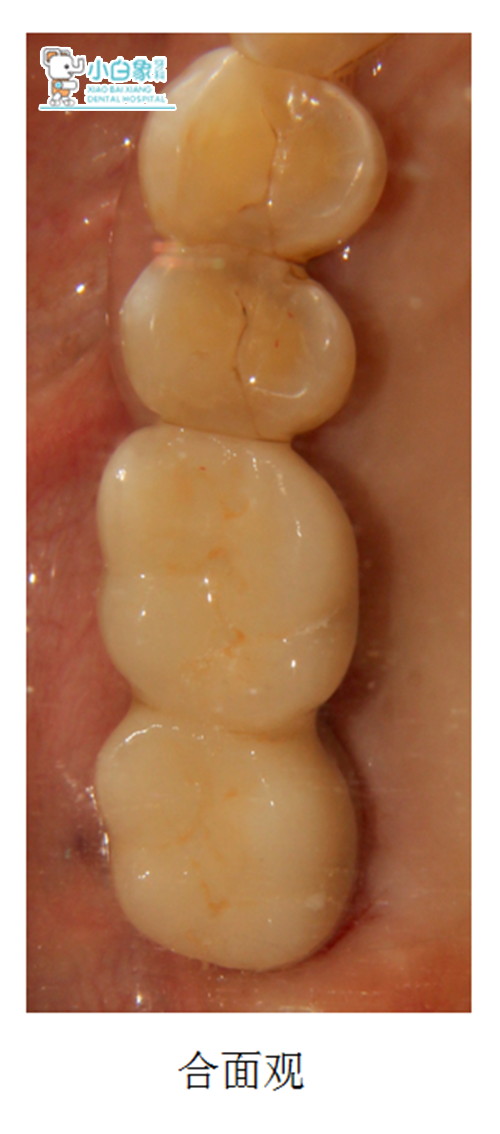

治疗过程:16 17去除愈合基台后,敲击就位修复基台,试戴全瓷冠,粘结。